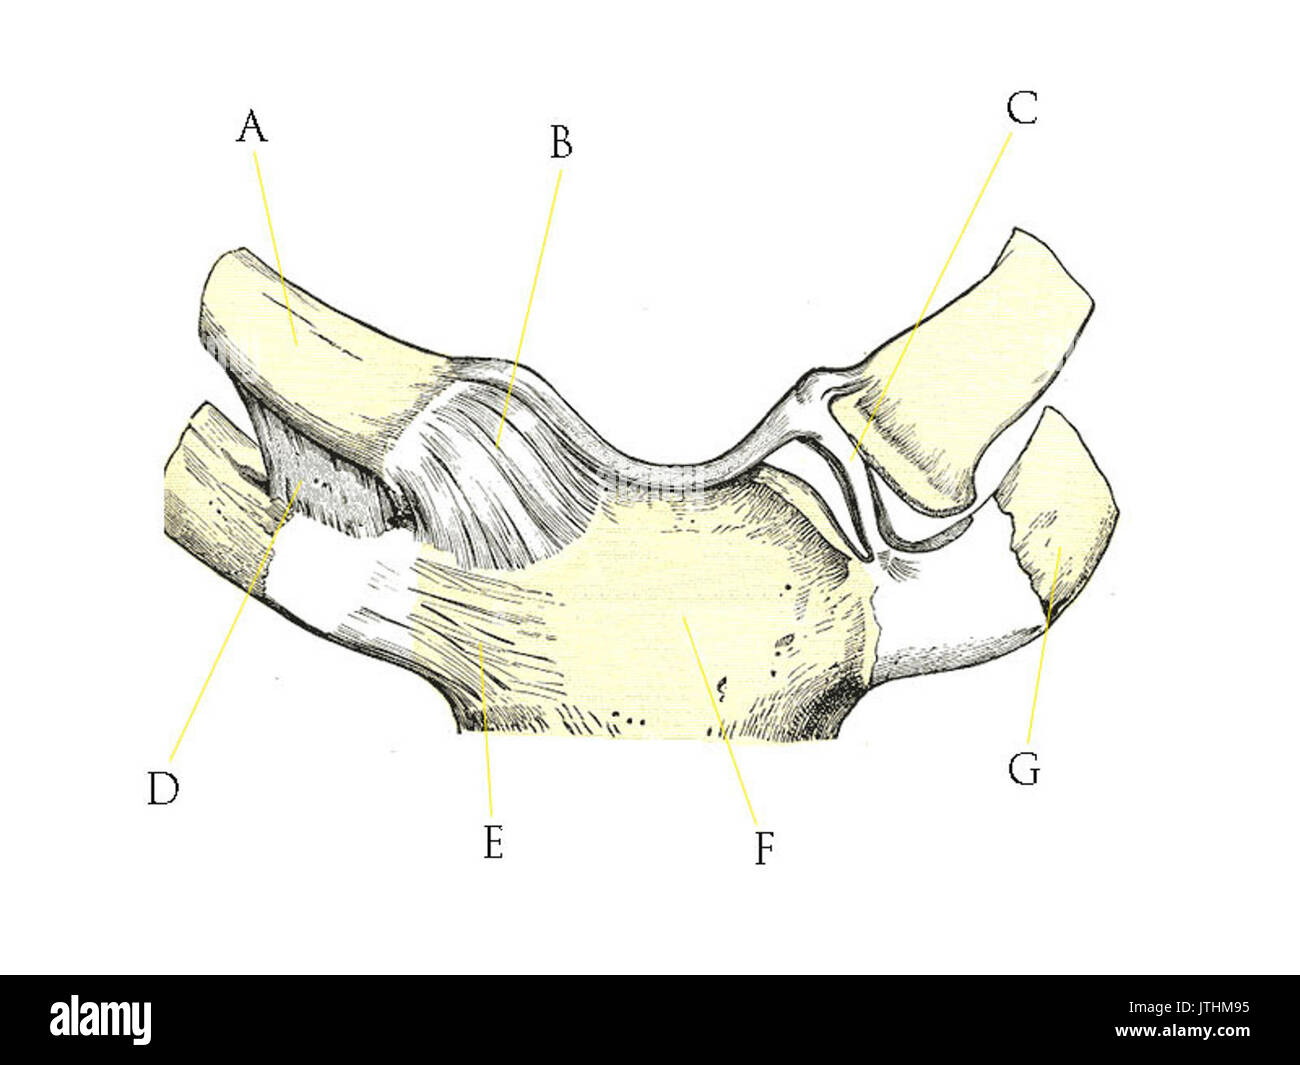

RF2BTGJYJ–Der Humerus ist ein langer Knochen des oberen Gliedes zwischen Ellenbogengelenk und Schulter, Vintage-Linie Zeichnung oder Gravur Illustration.

RF2BTHB20–Der Humerus ist ein langer Knochen des oberen Gliedes zwischen Ellenbogengelenk und Schulter, Vintage-Linie Zeichnung oder Gravur Illustration.